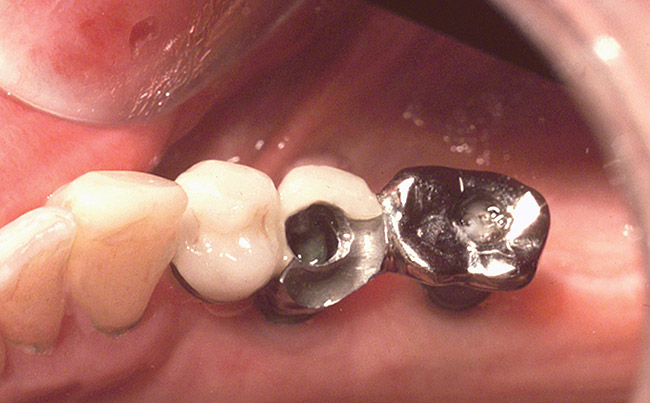

Figure 6  A fractured porcelain-fused-to-metal, implant-retained fixed partial denture. This prosthesis was cement-retained and difficult to remove from the underlying abutments.

Figure 6